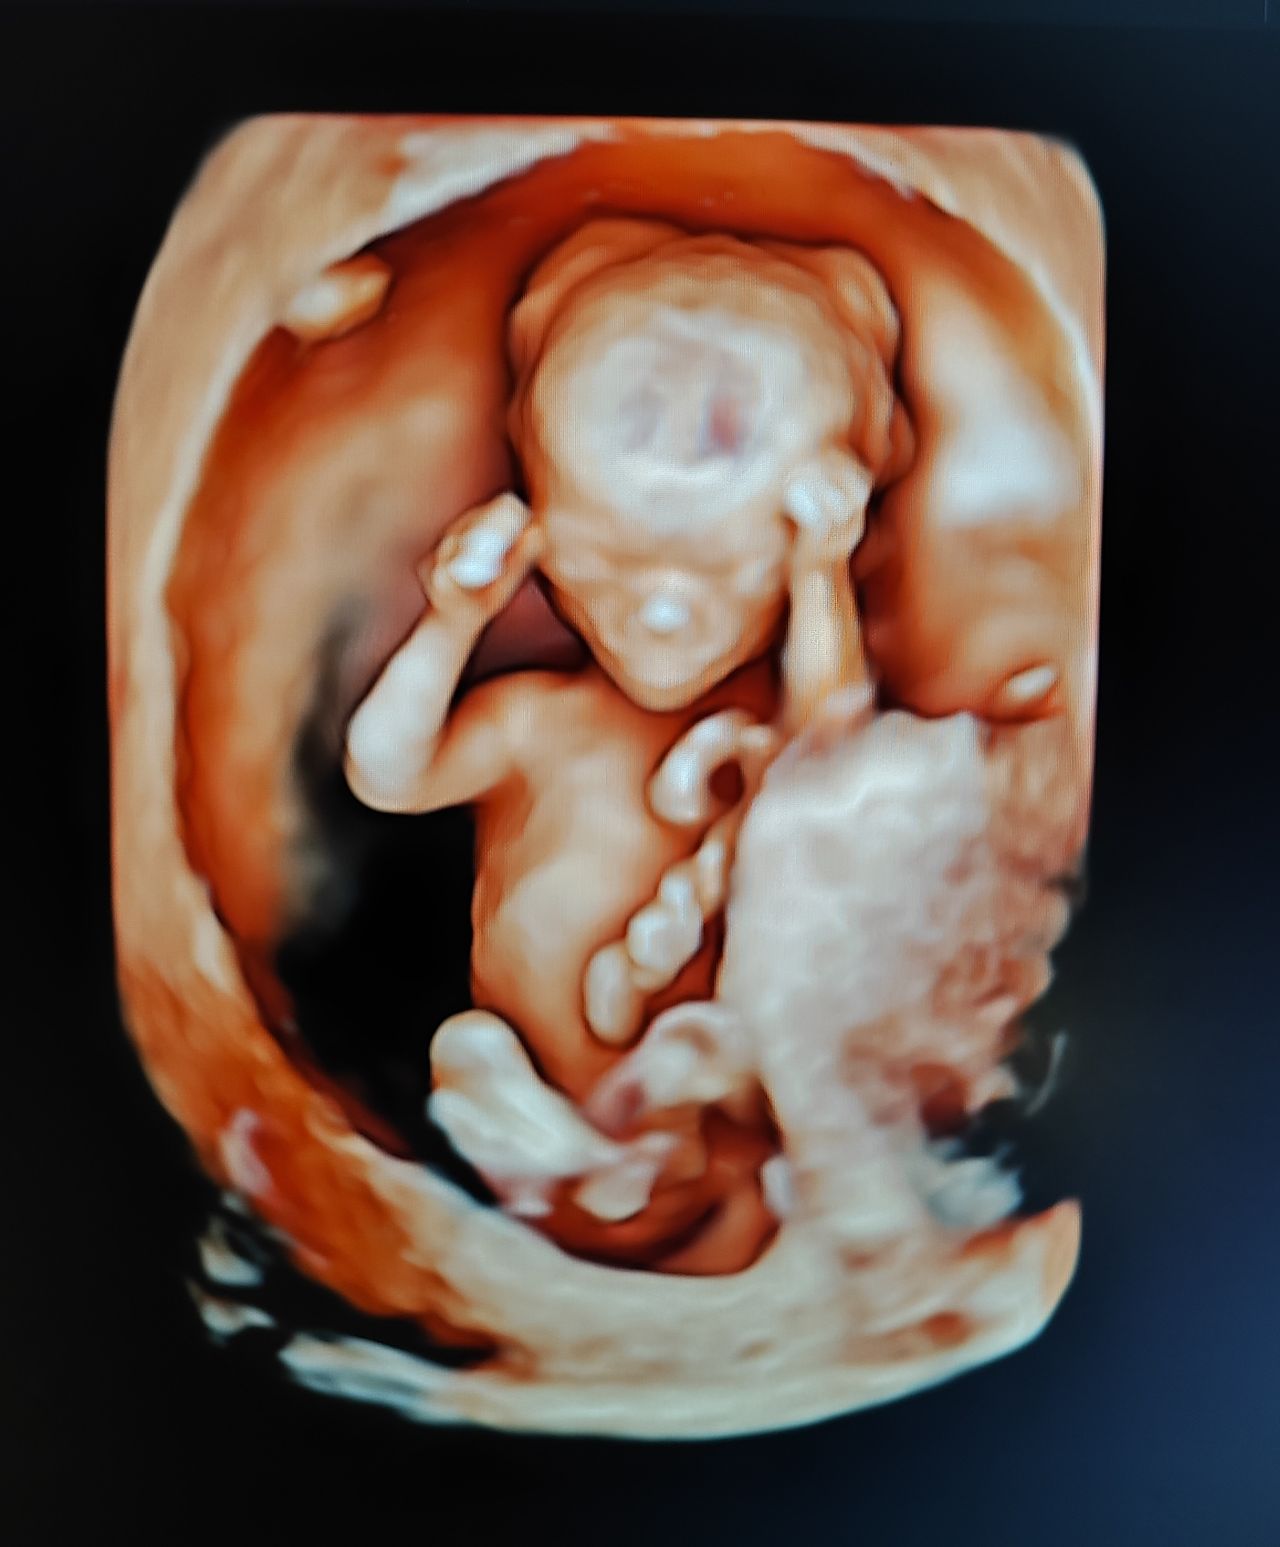

Dal 2015 al 2016 , frequenza presso U.O. Santa Maria delle Croci , Ravenna , periodo di Training di Chirurgia Laparoscopica, Endoscopica e di Isteroscopia ambulatoriale /office. In quell'anno nella stessa sede , ho  frequentato L'Ambulatorio di Diagnosi Prenatale acquisendo competenze in Ecografia Ostetrica del I-II-III trimestre.  Dopo la specializzazione ho proseguito la formazione e l'aggiornamento in particolare occupandomi dell’ Ecografia in ambito Ostetrico.

Ho acquisito "Certificate of Competence " da parte della Fetal Medicine Foundation per l'ecografia dell'11-13 settimana di gravidanza .

Da Maggio 2017 ad oggi faccio parte dello STAFF dell’Unità Operativa di Ostetricia e Ginecologia presso l’Ospedale "degli Infermi" di Faenza e dell’Ospedale "Morgagni Pierantoni "di Forli e mi occupo principalmente di Ostetricia , Gravidanza a Rischio, e dell'Ambulatorio Diagnosi Prenatale dove eseguo ecografie genetiche del I trimestre ed ecografie morfologiche e del III trimestre di gravidanza .